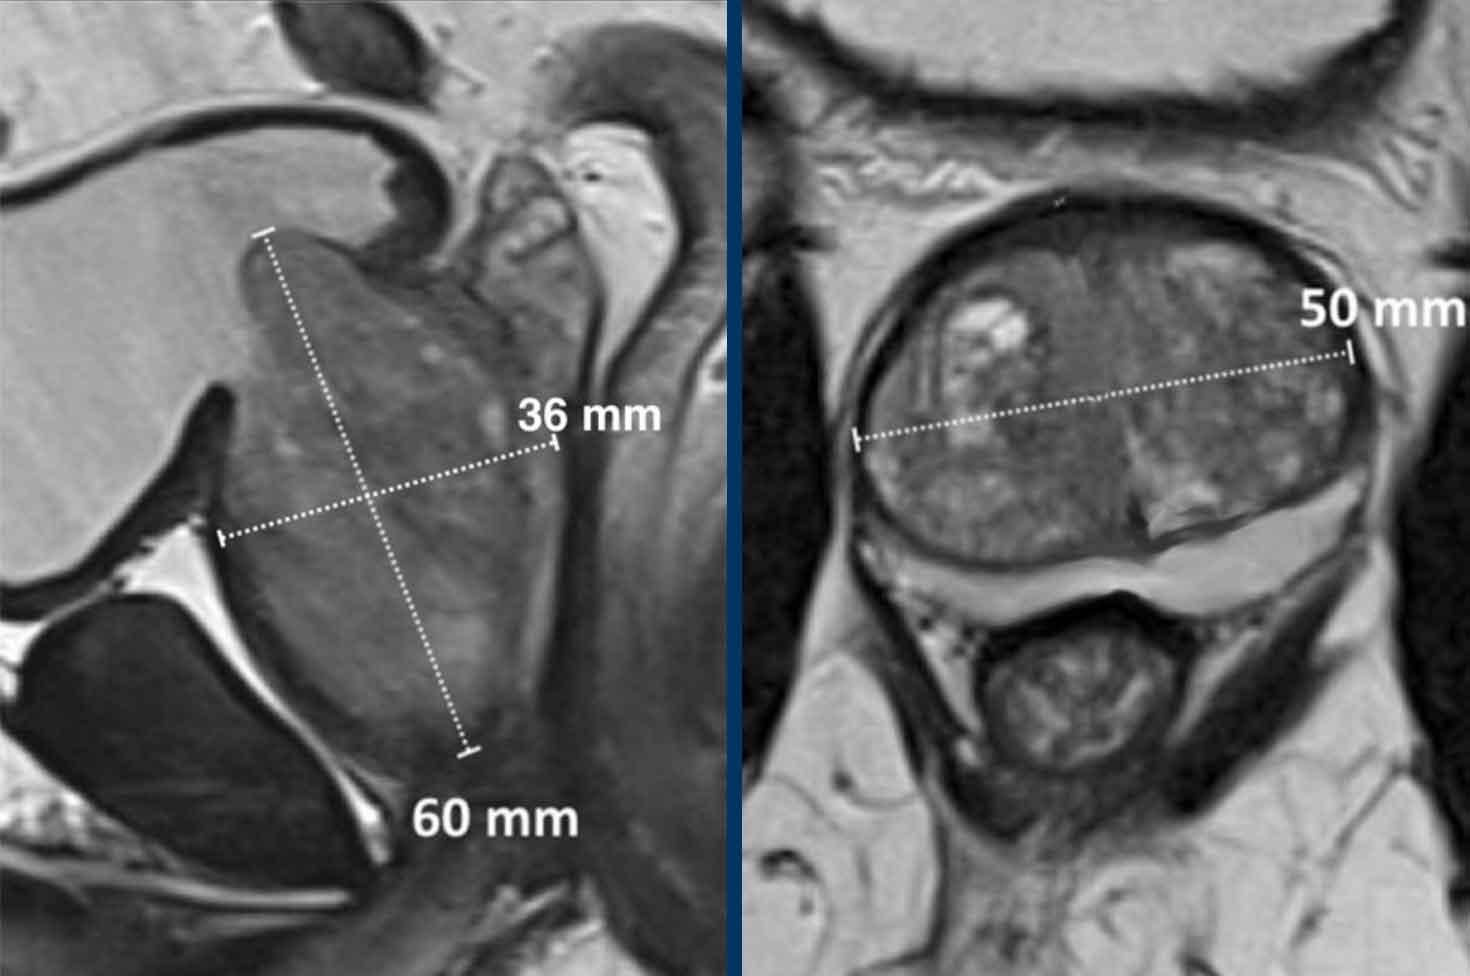

Thể tích tuyến tiền liệt và mật độ PSA

Trong trường hợp này, các kích thước của tuyến tiền liệt là 36 x 50 x 60mm (AP x LR x CC).

Thể tích tính được là 0,52 x (3,6 x 5,0 x 6,0) = 56,2 cc.

Nồng độ PSA của bệnh nhân này là 5.

Mật độ PSA là 5 : 56,2 = 0,09.

Đây là mật độ PSA thấp và bệnh nhân này có thể không có ác tính có ý nghĩa lâm sàng.

Công thức hình elipsoid:

Đường kính AP tối đa và đường kính dọc tối đa trên ảnh chuỗi xung T2W mặt phẳng đứng dọc giữa, nhân với đường kính ngang tối đa trên ảnh chuỗi xung T2W mặt phẳng ngang, sau đó nhân với 0,52.